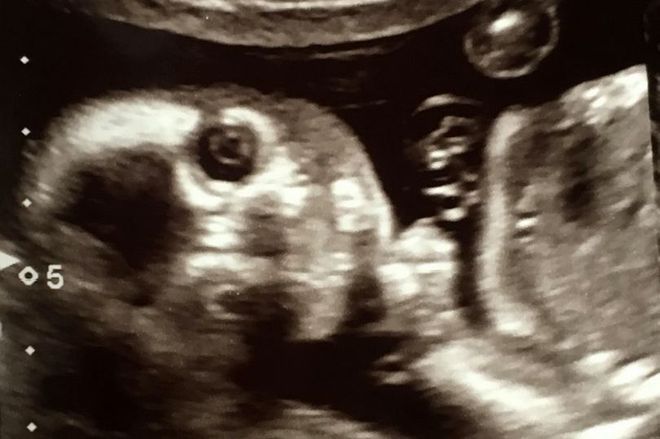

Uma mãe adolescente passou por situação semelhante no meio de um ultrassom. Ela viu o que parecia ser um "rosto alienígena" nas imagens. Veja a seguir!

A adolescente Sophie Scott, 16, de South Shields, na Inglaterra, ficou chocada ao encontrar uma "face alienígena" no ultrassom de seu bebê. As informações são do tabloide britânico Mirror

A mãe de primeira viagem, que está esperando o bebê com seu parceiro Stephen, 24, falou sobre o susto

"Fiquei com medo de o alien comer meu bebê", falou a jovem

"Nós vimos os olhos extras e aquela cabeça estranha atrás da criança". disse

"Eu tinha um ex-namorado que era fissurado em extraterrestres, acho que isso pode ser ele me perseguindo", brincou a garota

"Nós estamos brincando agora, mas eu realmente fiquei assustada já que ninguém conseguia identificar o que era aquilo", afirmou

O nascimento da criança é esperado para outubro e Sophie brincou com a proximidade da data com o Halloween

"Espero que ela não nasça no Halloween, isso seria assustador demais", concluiu